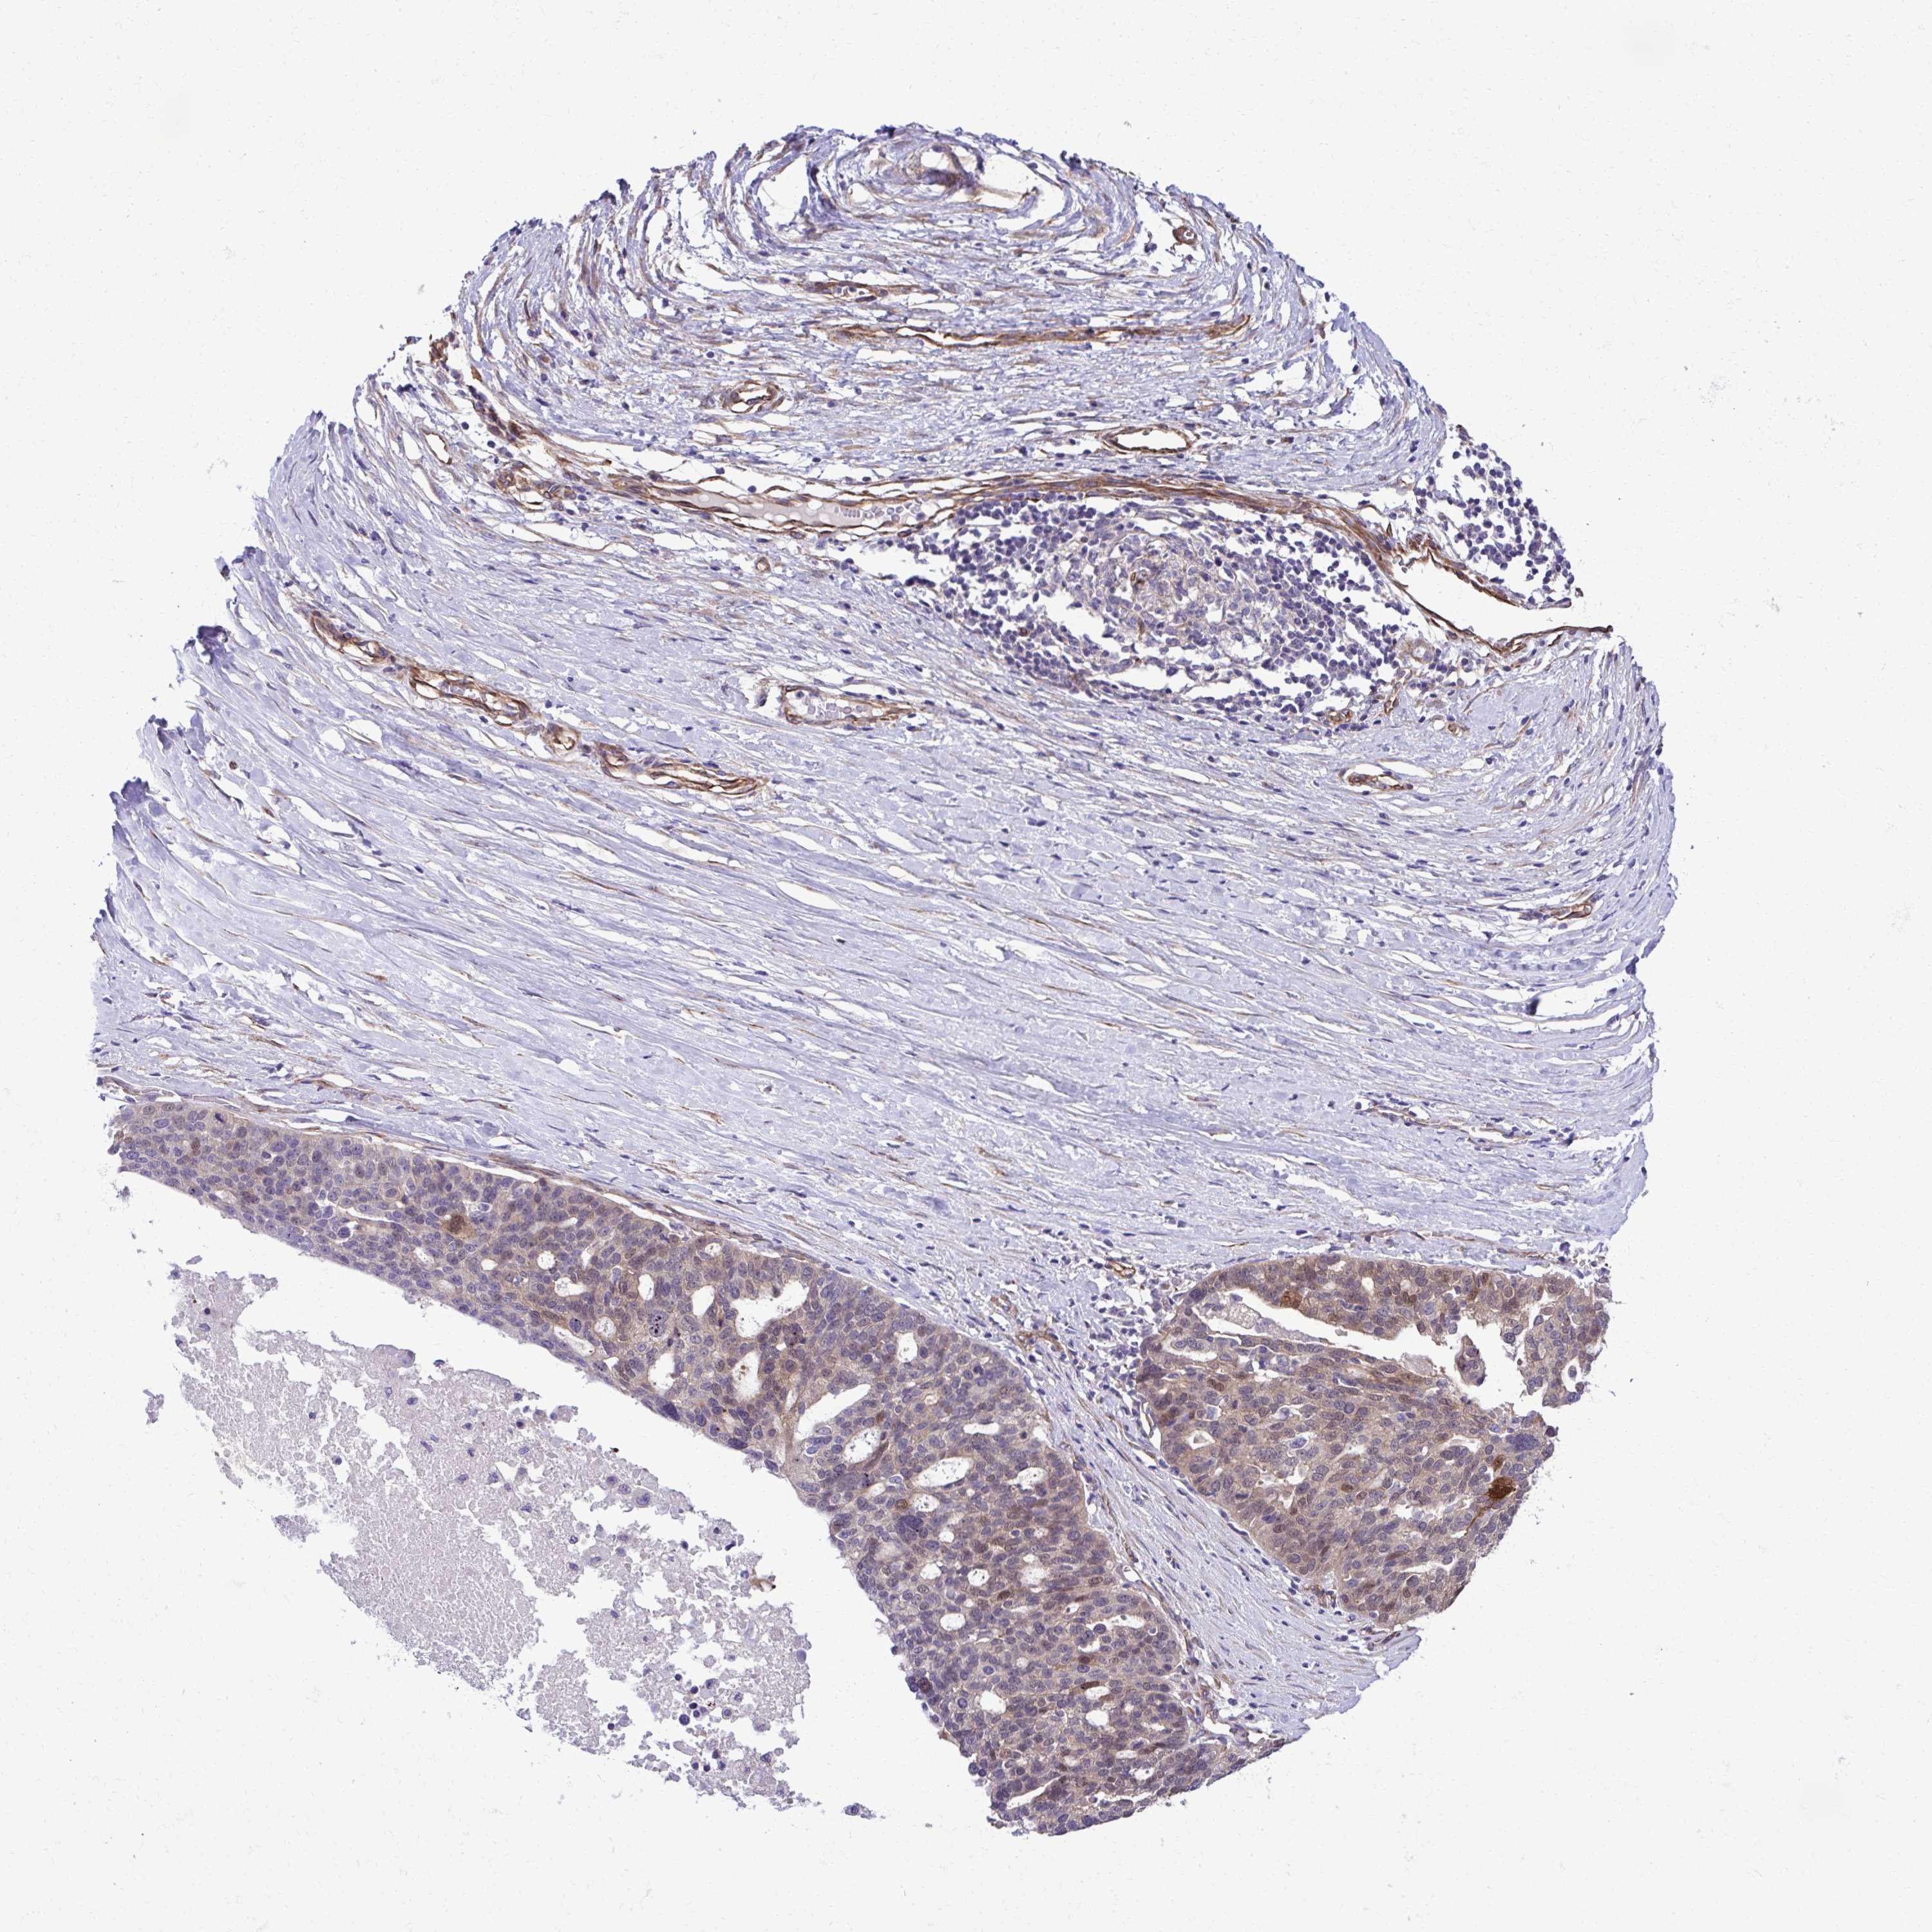

OVARIAN CANCER - Protein expressioni

A mouse-over function shows sample information and annotation data. Click on an image to view it in a full screen mode. Samples can be filtered based on level of antibody staining by selecting one or several of the following categories: high, medium, low and not detected. The assay and annotation is described here.

Note that samples used for immunohistochemistry by the Human Protein Atlas do not correspond to samples in the TCGA dataset.

Antibody stainingi

Antibody staining in the annotated cell types in the current human tissue is reported as not detected, low, medium, or high, based on conventional immunohistochemistry profiling in selected tissues. This score is based on the combination of the staining intensity and fraction of stained cells.

Each image is clickable and will lead to virtual microscopy that enables deeper exploration of all samples and also displays staining intensity scores, fraction scores and subcellular localization as well as patient and tissue information for each sample.

Antibody HPA056819

Staining

High

Medium

Low

Not detected

Intensity

Strong

Moderate

Weak

Negative

Quantity

>75%

75%-25%

<25%

None

Location

Nuclear

Cytoplasmic/membranous

Cytoplasmic/membranous,nuclear

Cystadenocarcinoma, serous, NOS

Carcinoma, endometroid

Cystadenocarcinoma, mucinous, NOS

Carcinoma, NOS